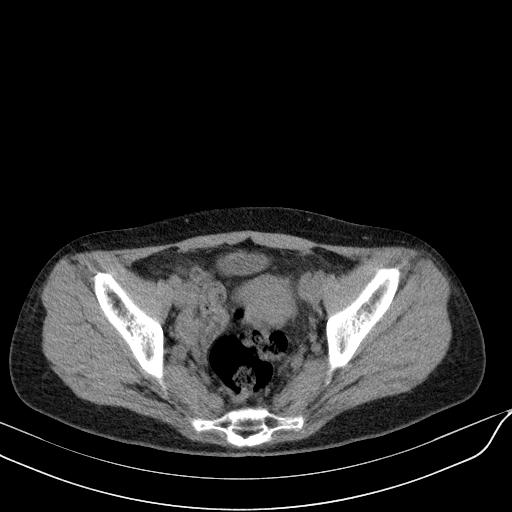

标题: CT23965:无外伤史,下腹痛 [打印本页]

标题: CT23965:无外伤史,下腹痛

肠道未准备,继续往下扫,乙状结肠占位不排除。建议钡灌或结肠镜检查。

乙状结肠占位不排除

回肠间质瘤?

肠道肿瘤,建议行钡剂灌肠检查。